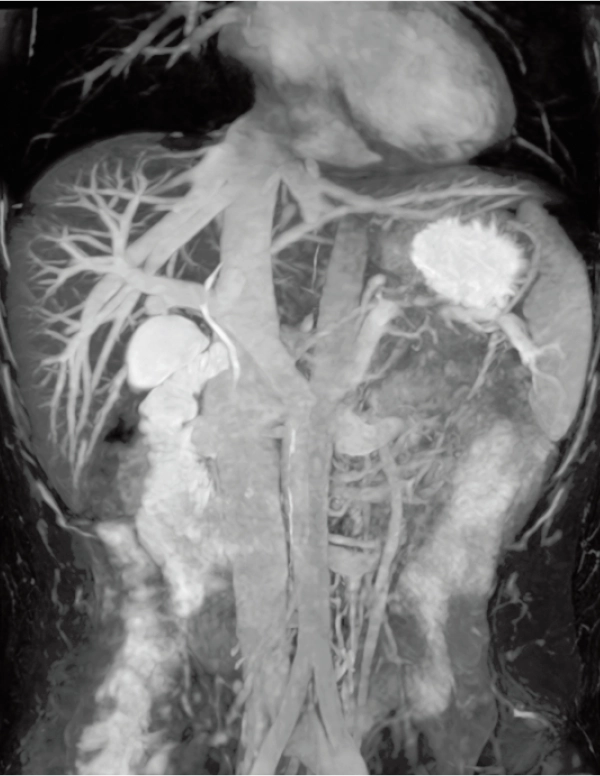

3D MRCPA (MIP)

Lower extremity